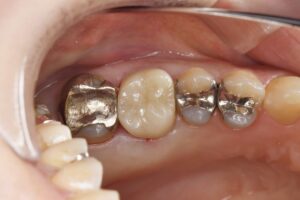

歯内療法専門医と連携して治療を行なった症例です。

虫歯と痛みが大きい部位に関しては、保険適応外の根管治療専門医が精密根管治療を行い、その後被せ物をジルコニアにて行いました。

| 精密根管治療後のジルコニアセラミック(20代女性) |

| 精密根管治療後、ジルコニアセラミックによる補綴修復を行なった。 |